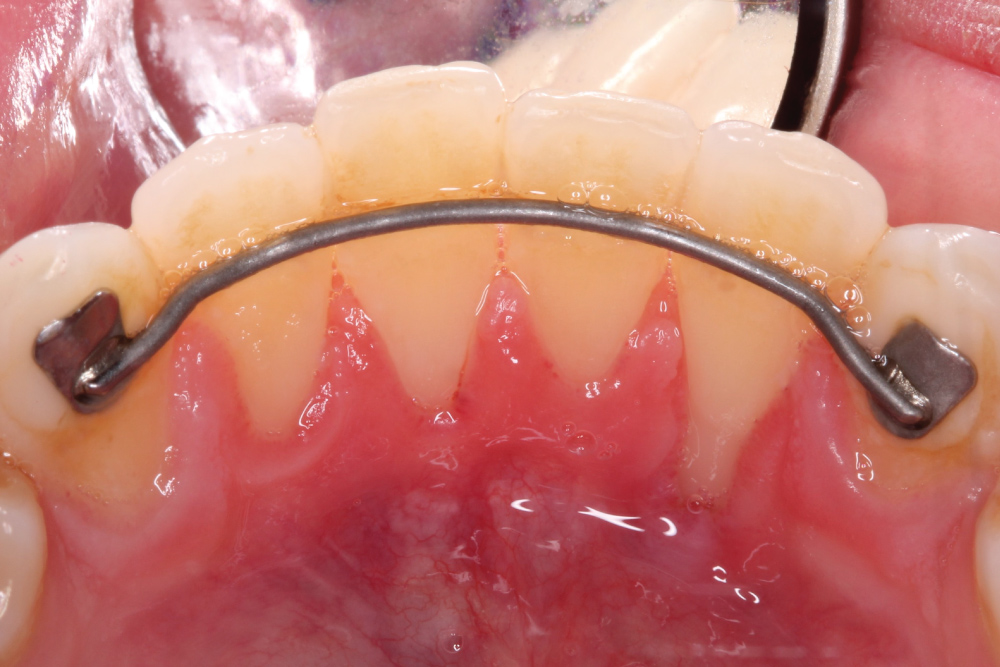

A sub-epithelial connective tissue graft (SCTG) was harvested using double parallel incisions as described by Harris on palate which was approximately 15 mm in length [9] (Figure 3). The donor site was closed by cross mattress stabilizing sutures using 4.0 chromic gut. Stabilizing sling suture was utilized to stabilize the connective tissue graft at the recipient site. The graft was tunneled laterally underneath adjacent papilla. 5.0 chromic sutures were used to sling the graft to #23 (Figure 4). After the SCTG was fixed by the sling sutures to the lingual exposed root surface at the CEJ, lateral margin of recession was approximated to cover the graft and closed with 6.0 polypropylene sutures. Simple interrupted loop sutures were utilized to close margins (Figure 5 and Figure 6). Only a minimal amount of connective tissue graft was exposed after approximating the lateral margins. Hemostasis was achieved with compression by a gauze.

Figure 4: The graft was tunneled laterally underneath adjacent papilla with 5.0 chromic gut sutures. View Figure 4

Figure 5: SCTG in place against the recession of #23. View Figure 5

Figure 6: Margins of the sub-periosteal tunnel approximated with 6.0 polypropylene sutures. View Figure 6